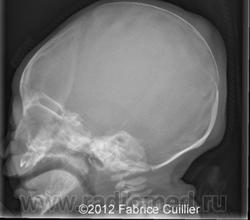

Врожденный порок развития средних отделов лица, характеризующийся плоским носом, втянутой субназальной областью (псевдопрегнией), укорочением альвеолярного отростка верхней челюсти, выпуклой верхней губой, атрофией слизистой оболочки носа без нарушения обоняния.

Рентгенологическая картина

Аплазия или гипоплазия костей носа, альвеолярного отростка верхней челюсти, лобных пазух.